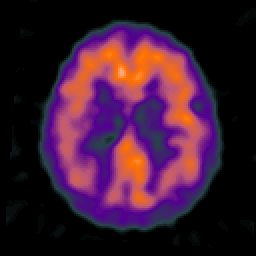

Alzheimer's disease: overlay -- Slice #17

[Home][Help][Clinical] Slice 17